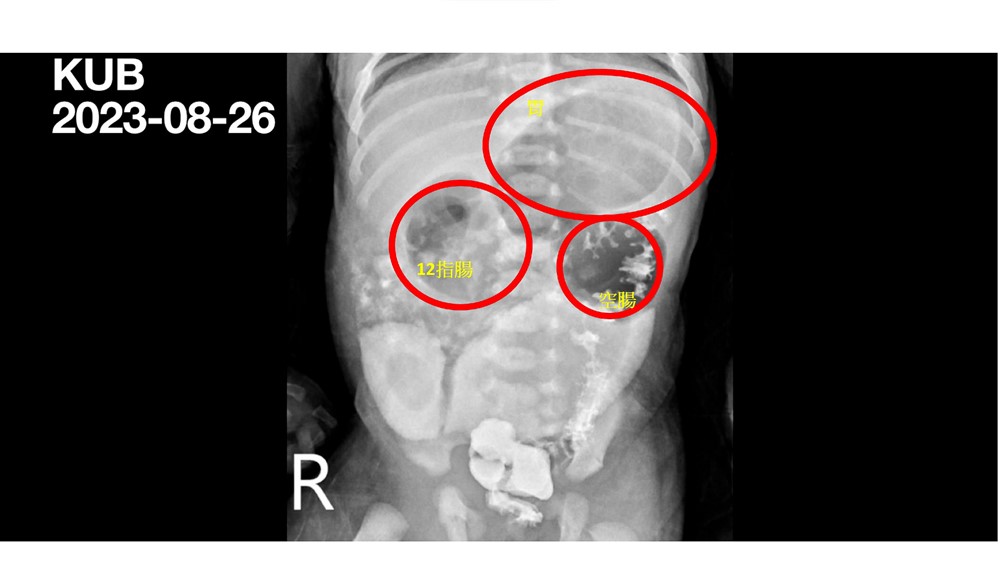

腸胃道腫大:腹部X 光攝影檢查明顯看見因為腸道閉鎖造成的腸胃道腫大。

蕭宇超醫師表示,小腸由十二指腸、空腸及迴腸組成,新生兒小腸閉鎖發生率約萬分之一點三到三點五,通常是胚胎發育時出問題,治療上幾乎都需要藉由外科矯正手術協助。而小寶的症狀是在空腸的部位完全閉鎖,無法進食的小寶只能透過靜脈注射的方式來補充營養,出生時體重兩千八百公克,出生三天轉院到花蓮慈院時體重掉了三百公克,到院後馬上進行手術治療,術後第四天嘗試少量進食,術後第十一天就可以完全脫離靜脈營養針,全靠自己喝奶,出院時體重回到兩千八百公克。